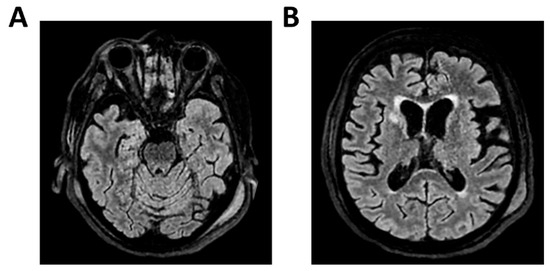

Figure 4.

MRI of patient 4 group 1. A 46-year-old HIV-positive woman with a history of substance abuse, alcohol use, heavy smoking, and on methadone therapy was admitted to the ER after a fall with head trauma. Cranial CT revealed a hypodense, heterogeneous lesion in the right nucleus-capsular region. Chest CT showed pseudonodular lesions, parenchymal consolidations (lingular and posterior-basal left lung), bilateral fibrous-scar tissue thickening, and polylobulated thickening in the right upper lobe. Due to respiratory deterioration, she was intubated and admitted to the ICU. Infectious disease consultation revealed severe immunosuppression (CD4 count 37/mm3), high HIV and HCV viral loads, and positive toxoplasmosis serology. She was not on antiretroviral therapy. Transferred to a specialized ICU, she was diagnosed with neurotoxoplasmosis. On day 2, TCCD showed altered CBF with PI of 1.96 on the right and 1.25 on the left, indicating possible intracranial hypertension. (A) 3D axial FLAIR sequence shows multiple bilateral supratentorial and infratentorial hyperintense areas. (B) Some of these areas present diffusion restriction in axial DWI sequence with the largest located in the right basal ganglia with moderate compression on the third ventricle. (C) One of these areas in the right middle frontal gyrus shows “ring enhancement” in the 3D axial T1 FSPGR after administration of contrast medium.

Figure 5.

MRI of patient 5 group 1. A 76-year-old diabetic woman was admitted to the ER for confusion, slurred speech, hyperglycemia, dyspnea (SpO2 87% on room air), and recurrent syncopal episodes, the latest resulting in a fall with frontal head trauma. Brain CT and neck vessel angio-CT were negative for acute lesions. Chest CT revealed a D11 vertebral collapse (post-vertebroplasty), right rib fractures (4th–7th), and right basal pleural effusion with ventilation impairment. During hospitalization, she developed fever and a right facial rash suggestive of herpes zoster. Empiric therapy with Tazocin and Zovirax was started, later broadened to include Rocephin and Ampital. On day 4, the patient experienced a decline in consciousness, necessitating intubation and mechanical ventilation. CSF analysis via lumbar puncture was positive for Varicella Zoster virus (FilmArray). She was transferred to a specialized ICU. On the second day in the ICU, TCCD showed severe CBF alteration, with a PI of 3.6 and markedly impaired flow in the left MCA, indicating likely intracranial hypertension and poor perfusion. (A) 3D axial FLAIR sequence shows subtle soft hyperintensity in the right hippocampal region likely due to inflammatory phenomena. (B) No diffusion restriction in DWI or contrast enhancement, some small areas of hyperintensity in the bilateral corona radiata and centrum semiovale, suggestive of chronic vascular injury and soft tissue swelling in the left parieto-occipital region.

In contrast, two patients in the same group presented with elevated PIs. One patient with HIV and neurotoxoplasmosis exhibited bilateral flow abnormalities (PI 1.96 on the right; 1.25 on the left), with multiple supratentorial ring-enhancing lesions on MRI, suggestive of cerebral toxoplasmosis. The patient showed no significant clinical improvement at 28 days (Table 2 and Figure 4).

Another patient with Varicella-Zoster meningoencephalitis had a critically elevated left-sided PI (3.6) and MRI findings limited to hippocampal hyperintensity (Table 2 and Figure 5).

Despite subtle structural abnormalities, the patient died within 28 days of admission. In both cases, high PI values accompanied poor neurological outcomes, highlighting the prognostic role of TCCD in identifying impaired cerebrovascular reserve and autoregulation failure.